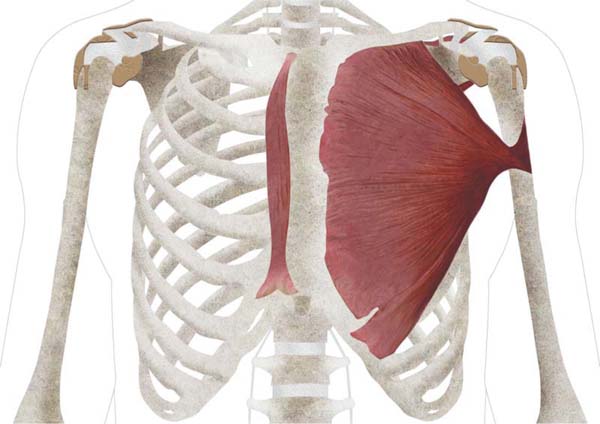

Durante o procedimento, ao elevar o músculo peitoral maior para criar um bolso de plano duplo para o implante, uma estrutura muscular incomum foi encontrada. O músculo, localizado superficialmente ao peitoral maior e paralelo ao esterno, foi identificado como o músculo esternal. Um desenho anatômico do músculo é mostrado na ► Fig. 1. Um vídeo (► Vídeo 1) e uma fotografia(► Fig. 2), obtidos durante a cirurgia, também são apresentados.

O músculo peitoral apresentava comprimento menor e não chegava ao esterno. Além disso, também parecia mais delgado em relação ao músculo contralateral. O músculo esternal media cerca de 8 cm de comprimento e 4 cm de largura, tinha orientação vertical e era bem vascularizado. Suas fibras estendiam-se da região torácica superior para baixo, acompanhando a parede torácica anterior. Sua estrutura era distinta tanto da do músculo peitoral maior quanto da do músculo reto abdominal, o que confirmou tratar-se do músculo esternal.